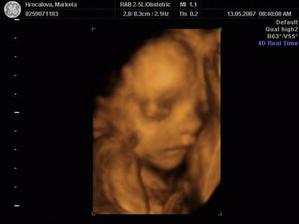

SRPŇÁTKA 2007 - fotky UTZ

album věnované mimískům, které se narodí v srpnu 2007 a jejich maminkám ze "Společného termínu SRPEN"